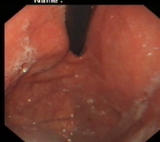

内镜下表现:黏膜红白相间,以白色为主,黏膜皱襞变平或消失,部分黏膜血管显露,可伴有黏膜颗粒或结节状等表现。如伴有肠化生于电子染色窄带成像放大内镜(NBI ME)下发现胃粘膜上皮细胞表面的脑回样结构嵴部的纤细浅蓝色线样结构。病理活检可进一步确诊。

萎缩胃表现